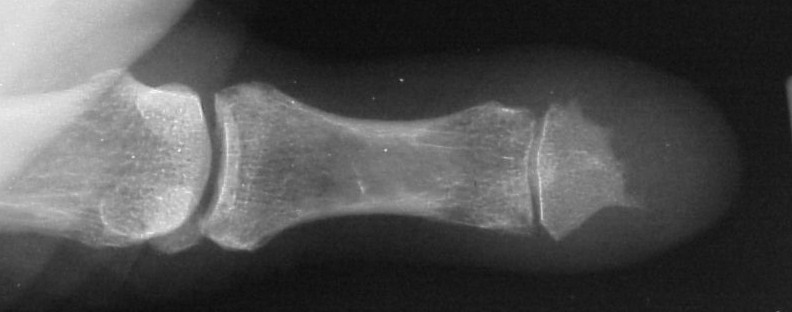

Plain films showed resorption of the distal two thirds of the distal phalanx:

Comparison views of the opposite side: